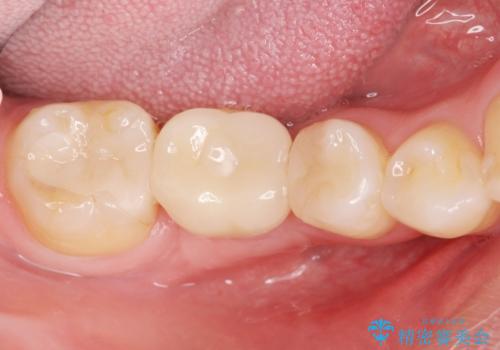

失った歯のインプラント補綴

- 歯の破折により失ってしまった右下の歯の機能回復を求めて来院されました。

取り外しの必要な入れ歯や、歯を大きく削る必要のあるブリッジではなく、インプラント治療を希望されました。